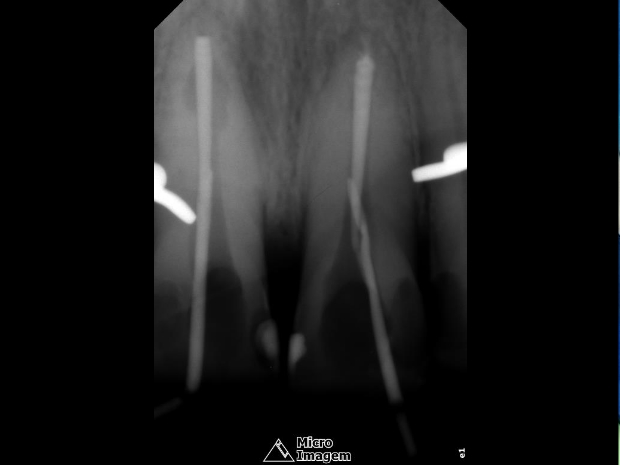

Após a abordagem inicial do paciente, o mesmo foi anestesiado e procedeu-se à confecção do isolamento absoluto. Posteriormente, o acesso coronário foi realizado, onde se constatou clinicamente a necrose pulpar de ambos os dentes. Foi realizada uma penetração desinfetante crown-down empregando como agente irrigador NaOCl a 5%, sendo a odontometria realizada pelo método radiográfico, devido a inviabilidade de emprego de um localizador foraminal nestas condições anatômicas, podendo influenciar em sua precisão (figura 4).

- Figura 4